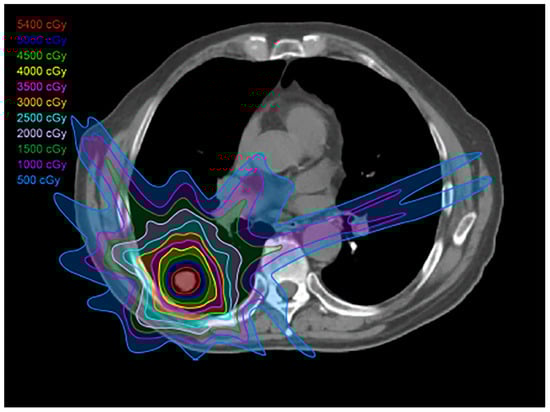

2.3. Intensity-Modulated Radiotherapy

2.4. Stereotactic Body Radiotherapy

2.6. Proton Therapy